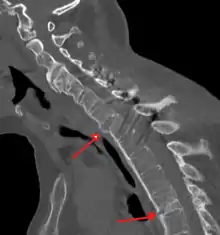

Imaging

X-rays

The earliest changes demonstrable by plain X-ray shows erosions and sclerosis in sacroiliac joints. Progression of the erosions leads to widening of the joint space and bony sclerosis. X-ray spine can reveal squaring of vertebrae with bony spur formation called syndesmophyte. This causes the bamboo spine appearance. A drawback of X-ray diagnosis is the signs and symptoms of AS have usually been established as long as 7–10 years prior to X-ray-evident changes occurring on a plain film X-ray, which means a delay of as long as 10 years before adequate therapies can be introduced.[24]

X-ray showing bamboo spine in a person with ankylosing spondylitis

CT scan showing bamboo spine in ankylosing spondylitis